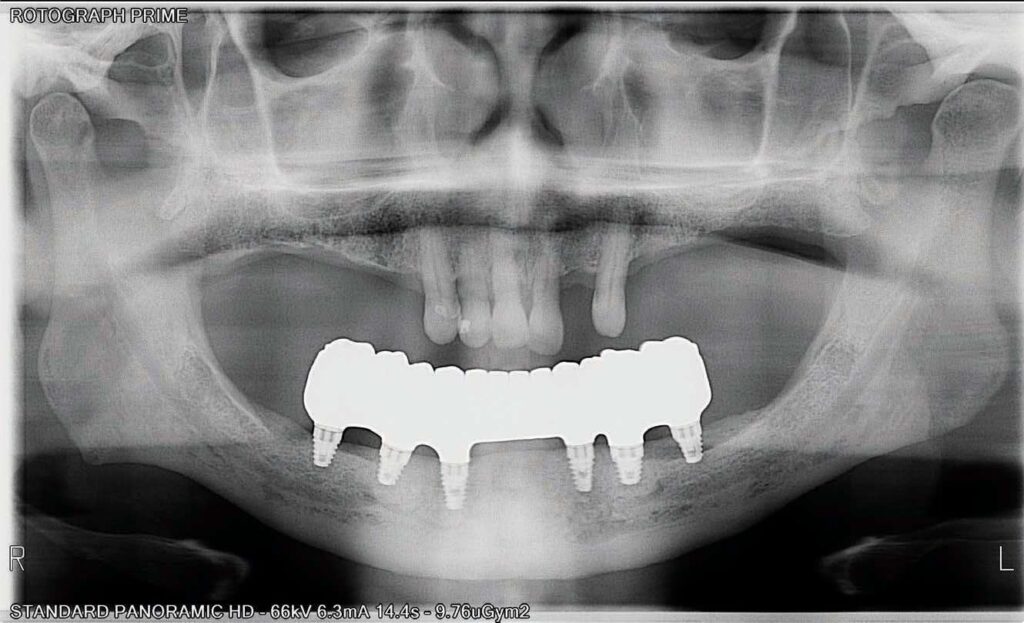

The completed BruxZir Full-Arch Implant Prosthesis is the culmination of great communication with the dental lab team. The final prosthetic result ensured that the patient would not only enjoy his new bridge but would also be able to clean and maintain it with one hand (Figure 20). The relaxed smile view and postoperative Panorex (Figures 21 and 22) shows appropriate lip and tooth display and was a vast improvement over his removable lower denture. The full-face, postoperative photo (Figure 23) of the pleased patient demonstrates that the dictates of aesthetic rehabilitation were met.

While the mandible is a “U-shaped” bone that requires ability to move in the x-, y-, and z-axes, the A-P spread of the implants ended close to the mandibular second bicuspid, which allowed for flexure of the mandible and ensured the patient did not have pain that may have been associated with splinting his entire mandible together in function from first molar to first molar. Short implants have been well documented in the literature for long-term success rates. The ability to place a fixed prosthesis against a removable partial also decreased forces of mastication and provided more relief in this case. Force factors, parafunction, implant length and width, and facial type and sex are all factors that must be assessed when deciding upon the ideal restorative plan for a patient.